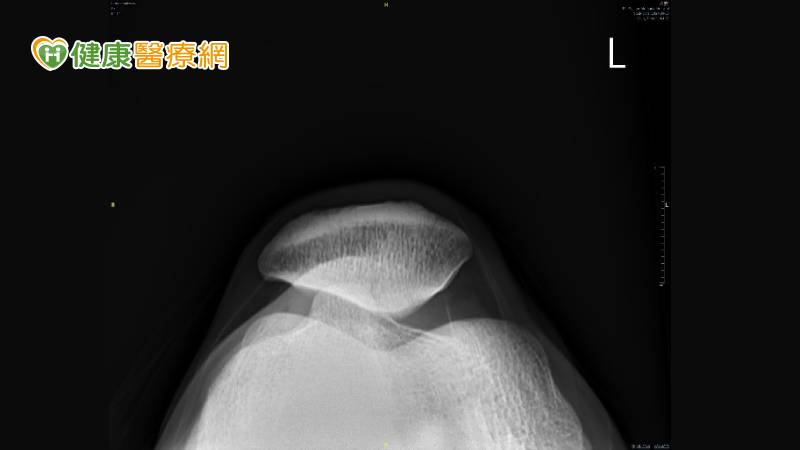

髕骨股骨疼痛症候群的患者常會有跑步時覺得膝蓋內外側的疼痛,或是蹲下站起時膝蓋卡卡或疼痛、膝關節僵硬腫脹、膝蓋彎曲時常有喀啦聲響。針對髕骨股骨疼痛症候群的檢查及診斷,可以藉由病史及理學檢查評估疼痛及受損部位,必要時並配合X光檢查髕骨外翻的程度(圖一)、超音波檢查內外髕支持帶有無受損(圖二)、核磁共振檢查髕骨下的軟骨有無受損情形。

▲(圖一)X光了解髕骨外翻的程度